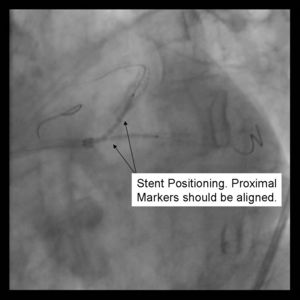

3) Both stents are advanced into the side branch and parent vessel. This may require further predilitation. Generally, the stents are advanced beyond the delivery point. Operator preference differs with respect to amount of overlap. Some operators form a long segment of overlap (>5mm), while others try to minimize overlap. It is absolutely essential that both vessels are covered during the balloon inflation. Optimal placement is ensured by advancing both stents distal to the intended deployment site then pulling them back into position. The proximal marker segements should be aligned, with positional confirmation in at least 2 separate views.